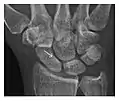

Figure 3: A 26-year-old man presenting with wrist pain after being assaulted. (a) Initial anteroposterior radiograph shows a subtle linear lucency within the scaphoid extending to the scaphocapitate articular surface that was overlooked (arrow). (b) Initial "scaphoid" view was negative. (c) Followup anteroposterior radiographs, 12 days later, shows obvious scaphoid fracture (arrows).[1]

Triquetral fracture usually occurs on the dorsal aspect by impingement from the ulnar styloid or avulsion of strong ligamentous attachment. The dorsal avulsion fracture or "chip fracture" appears as a small bony fragment on the dorsal aspect of the triquetrum and is best detected on the lateral view(Figure 4). When radiography is negative in patients with high suspicion of a fracture, both MRI and MDCT will be of value. However, it has been shown that MRI is superior for detecting trabecular fractures in carpal bones.